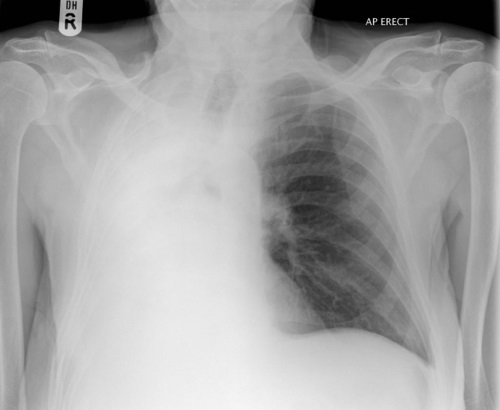

Lung collapse - note how the trachea is pulled towards the side of the white-out